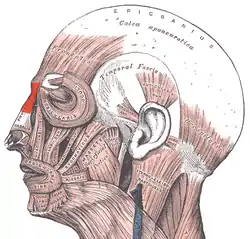

- Nasal muscles – The movements of the human nose are controlled by groups of facial and neck muscles that are set deep to the skin; they are in four functional groups that are interconnected by the nasal superficial aponeurosis—the superficial musculoaponeurotic system (SMAS)—which is a sheet of dense, fibrous, collagenous connective tissue that covers, invests, and forms the terminations of the muscles.

The movements of the nose are affected by

- the elevator muscle group – which includes the procerus muscle and the levator labii superioris alaeque nasi muscle.

- the depressor muscle group – which includes the alar nasalis muscle and the depressor septi nasi muscle.

- the compressor muscle group – which includes the transverse nasalis muscle.

- the dilator muscle group – which includes the dilator naris muscle that expands the nostrils; it is in two parts: (i) the dilator nasi anterior muscle, and (ii) the dilator nasi posterior muscle.